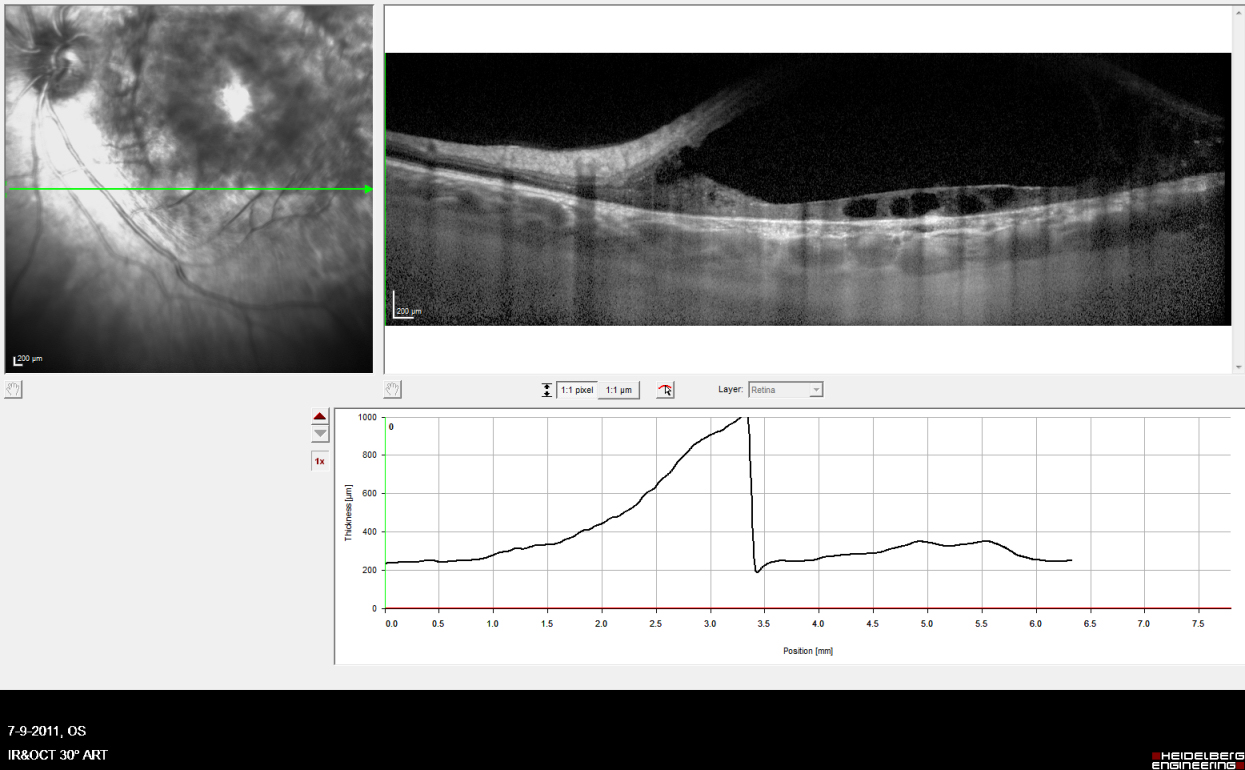

External examination of the eyes was normal, including corneal size (11 mm diameter OU) and palpebral fissure (Figure 1 [Fig. 1]). BCVA was 20/32++ in the RE and 20/200 in the LE (correction RE sph +5.25 cyl +1.50 axis 42 and LE +5.50 cyl +0.75 axis 109). Ocular tension was 17 mmHg RE and 18 mmHg LE. Biomicroscopic examination showed in both eyes a mildly reduced anterior chamber depth and a maculopathy (Figure 2 [Fig. 2]). Fluorescein angiography confirmed the presumed diagnosis of CSC OU with macular serous detachment, diffuse pigment epitheliopathy, and mild focal subretinal leakage (Figure 3 [Fig. 3]). Focal lasercoagulation was performed in the RE in 1995, 1996, 1997 and 1998, but despite this treatment the macular detachment increased slowly and cystic retinal degeneration and fibrosis became evident, as well in the RE as in the LE (Figure 4 [Fig. 4]). Repeated FA revealed progressively expanding subretinal lesions in the posterior pole of both eyes, with leakage, staining and pooling of fluid (Figure 5 [Fig. 5]). In 2004, PDT was available, and as the exudative lesions were pronounced, one session of SFR PDT was administered in the LE, however, without benefit. Over the last years of follow-up eye drops with dorzolamide were used, apparently without benefit. OCT was available in 1997, and repeated scans showed pronounced and progressive cystic degeneration of the macula OU (Figure 6 [Fig. 6]). EDI OCT, available in 2011, demonstrated dilated choroidal vessels and a thick choroid (Figure 7 [Fig. 7]). ICGA also showed dilated choroidal vessels (Figure 8 [Fig. 8]). Ultrasound A-scan biometry demonstrated OU reduced total axial length, reduced anterior chamber depth, reduced vitreous cavity and increased lens thickness (Table 1 [Tab. 1]). Recently, atrophic changes became evident (Figure 9 [Fig. 9]) and on OCT decreased retinal thickness was observed (Figure 7 [Fig. 7]). Autofluorescence imaging showed large areas of hypoautofluorescence compatible with afunctional retinal pigment epithelium and retina (Figure 10 [Fig. 10]). VA in 2011 was 20/800+ in the RE and 20/600 in the LE.

Figure 7: Index patient, OCT Spectralis EDI in 2011, at age 48. Note dilated choroidal vessels and a thick choroid, and cystic degeneration of the retina, with reduced thickness of the retina compared to previous recordings.